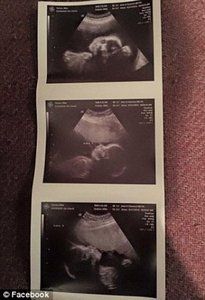

50 milyonda bir ihtimal gerçekleşti! 2 bedende 3 bebek!

Üçüzlerden ikisinin yapışık olduğunu öğrendiklerinde, hamilelik süreci onlar için daha da zorlaştı.